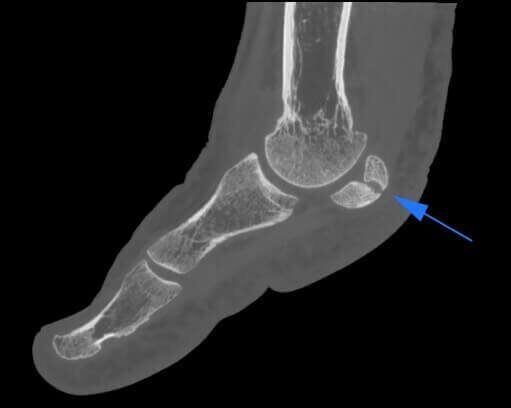

Os Trigonum